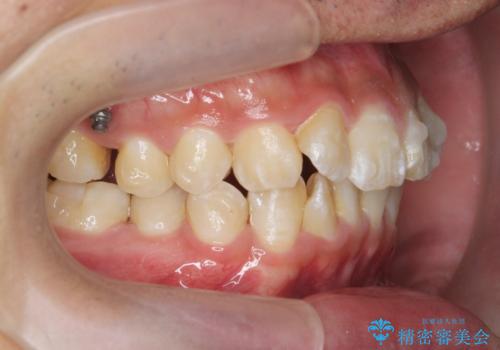

遠心移動を伴うマウスピース非抜歯矯正治療

- 「前歯の見た目を改善したい。」と矯正治療を希望され来院されました。

前歯のガタつきに加え、上顎が前にある咬合関係(上顎前突)を改善すべく、マイクロインプラントを用いた上顎奥歯の後方移動、拡大、ディスキングを用いたマウスピース矯正治療を計画します。

マイクロインプラントを使用したことで、しっかりと遠心移動が為され、良好な咬合関係が達成されました。